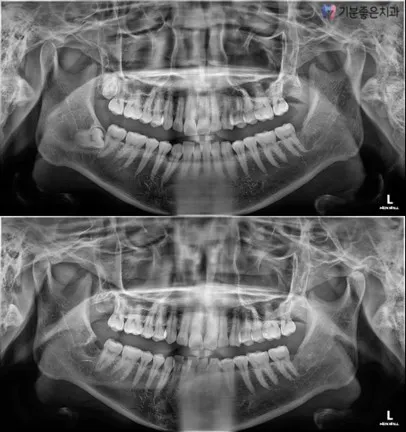

Types of Wisdom Teeth and Treatment Decisions

Treatment methods and difficulty vary significantly depending on the direction and position of wisdom tooth growth.

Partially Impacted Wisdom Tooth

These are wisdom teeth where only part of the tooth is exposed outside the gum. They are prone to food impaction and recurrent inflammation, so extraction is recommended in most cases.

Fully impacted wisdom tooth

This refers to a wisdom tooth completely buried within the gum or jawbone. Treatment direction is carefully determined after confirming the positions of surrounding teeth and nerves.